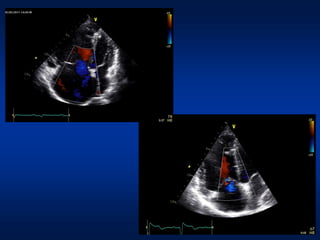

Paziente A Paziente B

donna, HIV+, anni 43 donna, IP idiopatica, anni 28

Classe WHO III Classe WHO II

6MWT: 470 mt

Fc 75 bpm; SO2 98%

Fc 106 bpm; SO2 97%

6MWT: 280 mt

Fc 90 bpm; SO2 95%

Fc 118 bpm; SO2 92%

BNP 890 pg/ml BNP 155 pg/ml

Cateterismo cardiaco destro

PAPm 40 mmHg

PW 9 mmHg

GTP 31 mmHg

CI 2.01 l/min/m2

PAD 13 mmHg

PVR 11 UW

PW 10 mmHg

GTP 30 mmHg

CI 2.45 l/min/m2

PAD 5 mmHg

PVR 6 UW